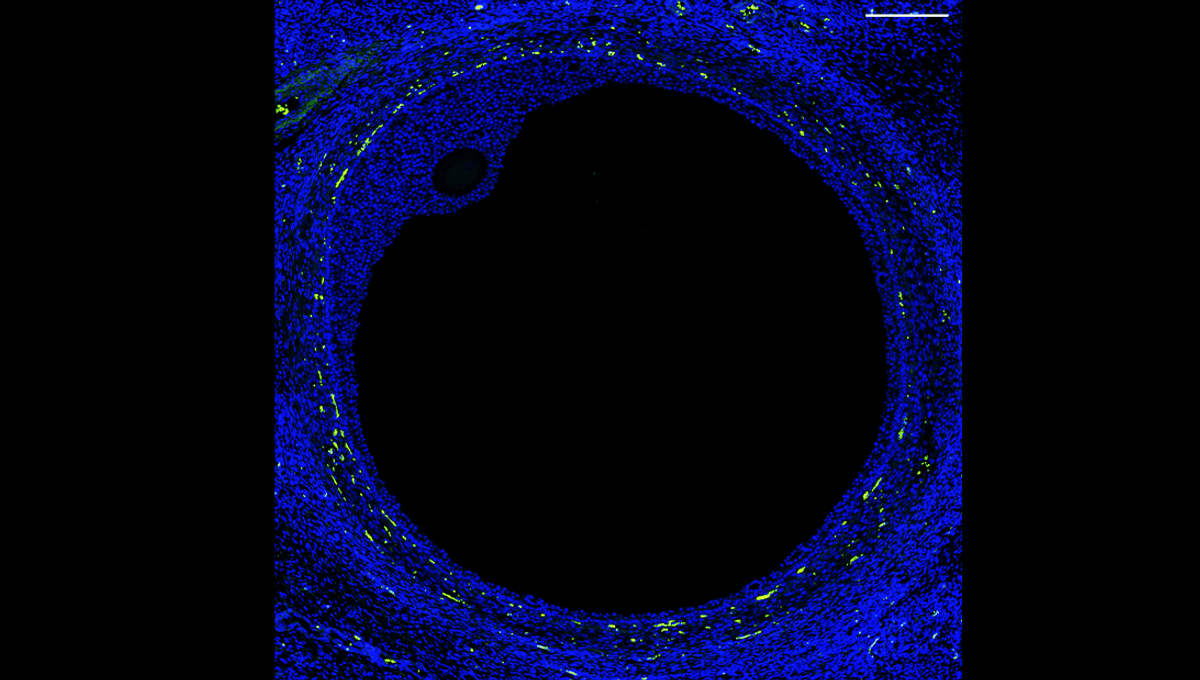

First-Ever Cell Atlas Of The Human Ovary Brings Artificial Ovaries A Step Closer To Reality

A female reproductive organ cell atlas? At last.